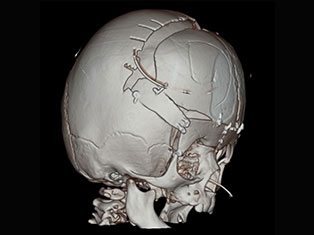

Brain Tumors

A brain tumor is a mass or growth of abnormal cells in your brain. Many different types of brain tumors exist. Some brain tumors are noncancerous (benign), and some brain tumors are cancerous (malignant).